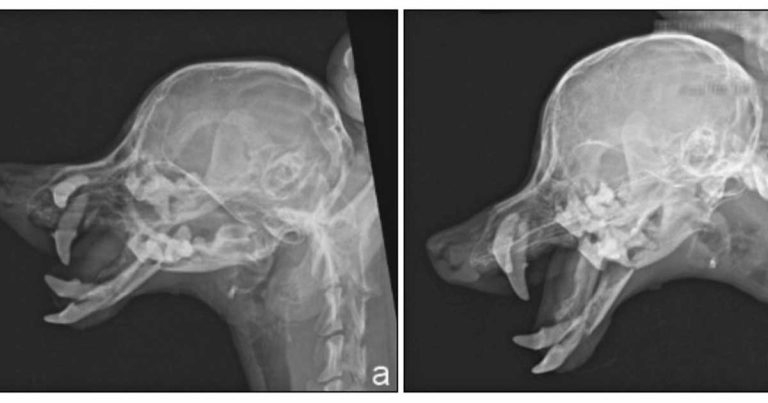

In most cases, diagnosis of mandibular and maxillary fractures is simple, and only based on the results of the clinical exam and radiographs. In more difficult cases, overlapping of bony structures and skull complexity can make radiographs non-diagnostic.

Radiographic examination could also be a challenge when it runs to find small fractures (Figure 1; Bar-Am et al, 2008). In these cases, CT scan is advisable (Figure 2). Usage of intramural dental radiographs would also reduce the risk of missing minor fractures and provide a better view of the roots of the teeth (Hale, 2015).